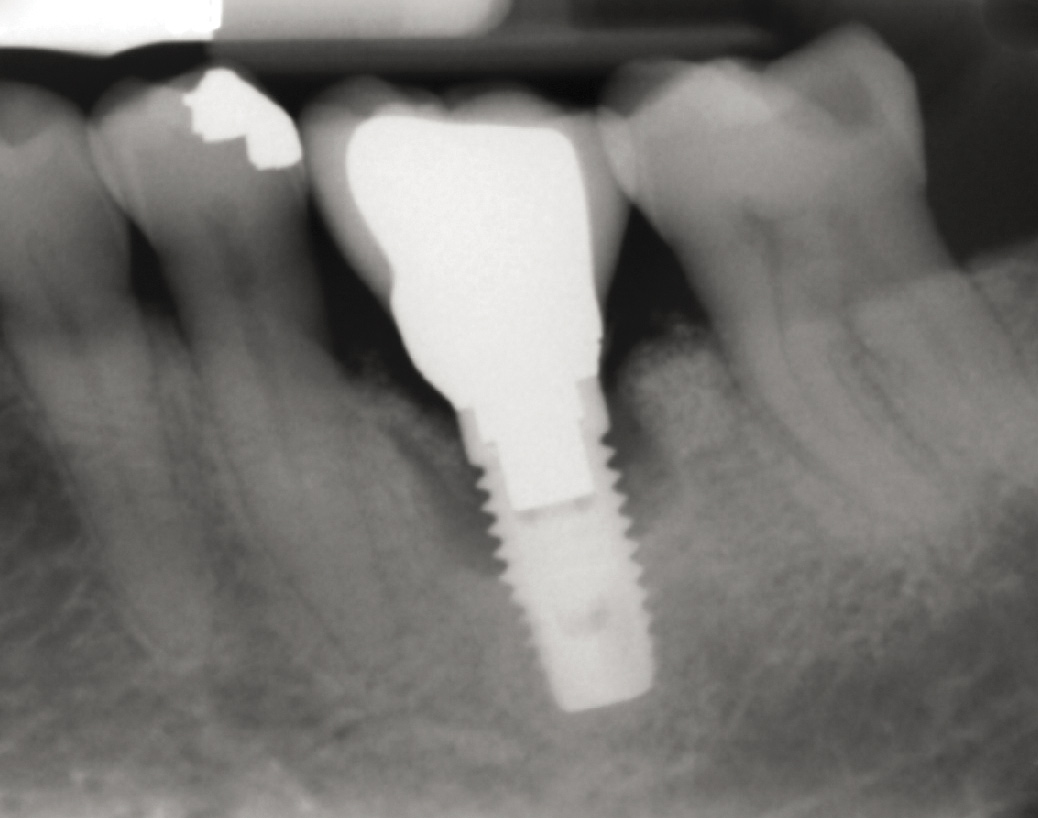

Fig 17. Radiograph showed symmetrical infrabony defect affecting 50% of the implant surface.

Figure 17

28. Seventeen-month post-treatment radiograph demonstrating bone close to the implant approximation and almost complete osseous fill of the original infrabony defect.

Figure 28